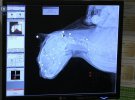

"Напівмертву тварину спочатку знайшла сусідка. Вона віднесла кота до підвалу. Три дні кіт пролежав на сходах. Думали, що впав із верхніх поверхів, або його погризла собака. Весь був у крові і із гематомами на голові. Температура тіла була 34 градуси, а це вже передсмертний стан. Два дні проводили реанімацію і відігрівали. Коли зробили рентген, то виявилось, що в голові і в шиї застрягло 26 куль. У новорічну ніч тварину розстрілювали впритул. Кіт пручався, тому був зламаний і хребет", - пояснила Олена Єдігарєва, зоозахисник.

Кота одразу віднесли до лікарні. Хірурги вперше оперували тварину в такому важкому стані.

"Спочатку годували тільки зі шприца. Вчора кіт підіймався на лапи і вже сам харчується. Йде на поправку. Виявилось, що зовсім не бачить. Швидше за все доведеться ампутувати око. Маємо надію, що врятуємо зір. 16 куль залишилось в тілі, адже витягти їх зараз без шкоди для здоров'я не можливо", - пояснила зоозахисник.